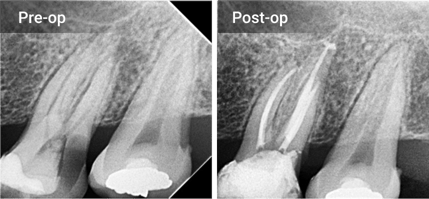

Excellent Radiopacity

The highly radiopaque and hydrophilic sealer provides tight

adhesion to both dentin and gutta percha points.

radiopacity@2x